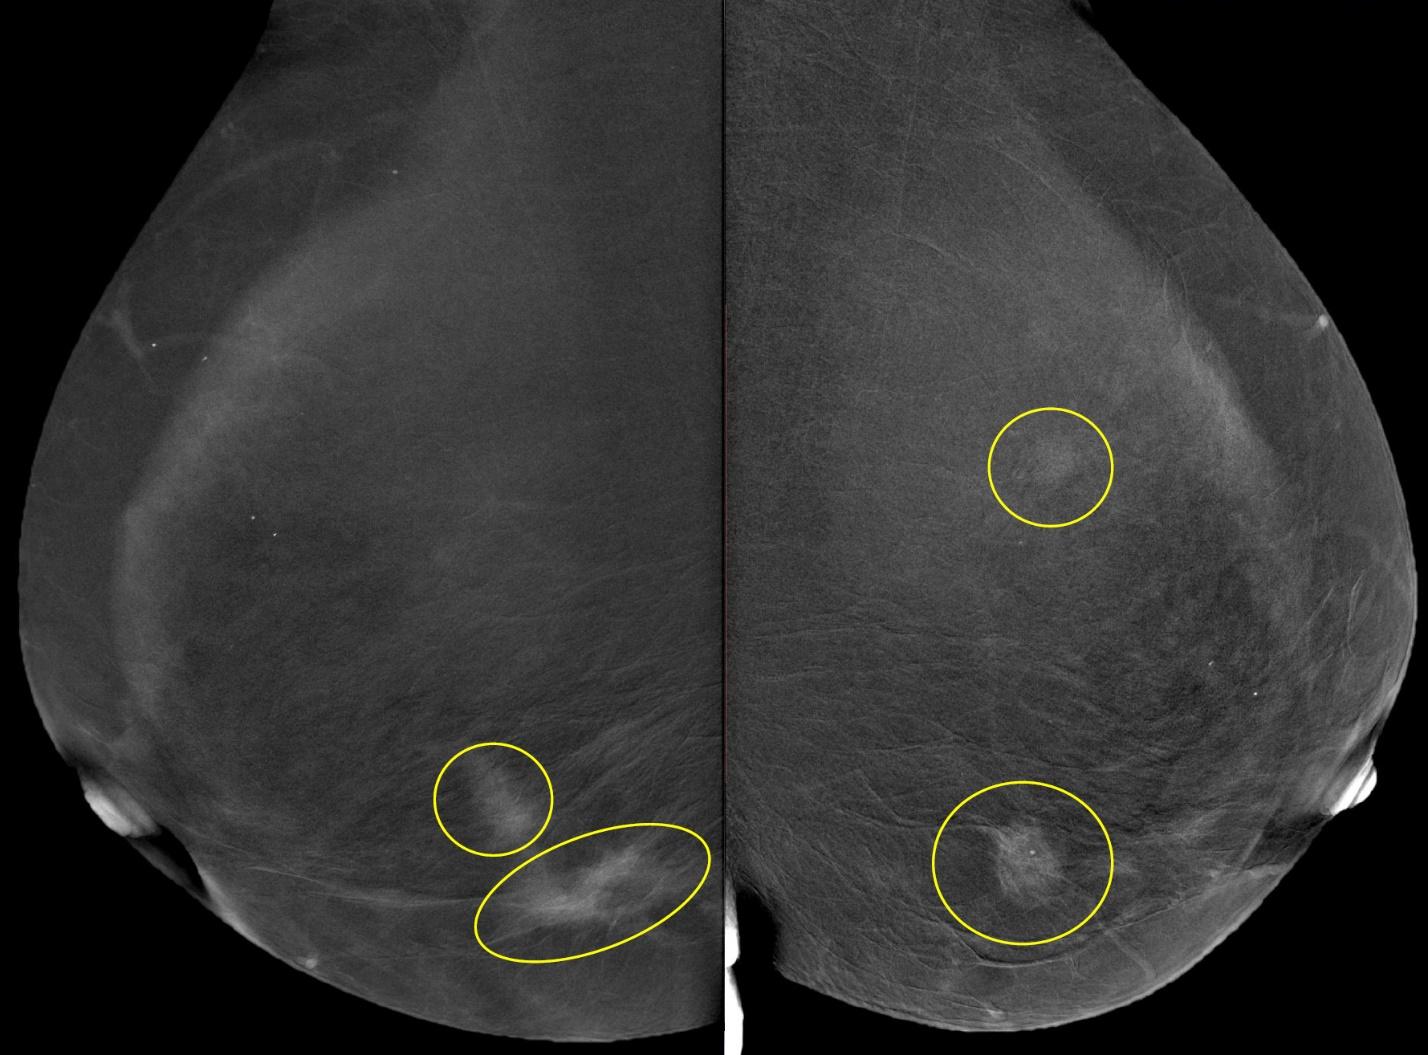

Метод прицельной маммографии с увеличением применяется для более детального исследования определенной области молочной железы. Он отличается высокой точностью диагностики. В отличие от обычной маммографии, которая предоставляет более общую информацию о состоянии молочных желез, прицельная маммография с увеличением позволяет получить точные данные о процессах, происходящих в тканях, благодаря методу компрессии конкретного участка.